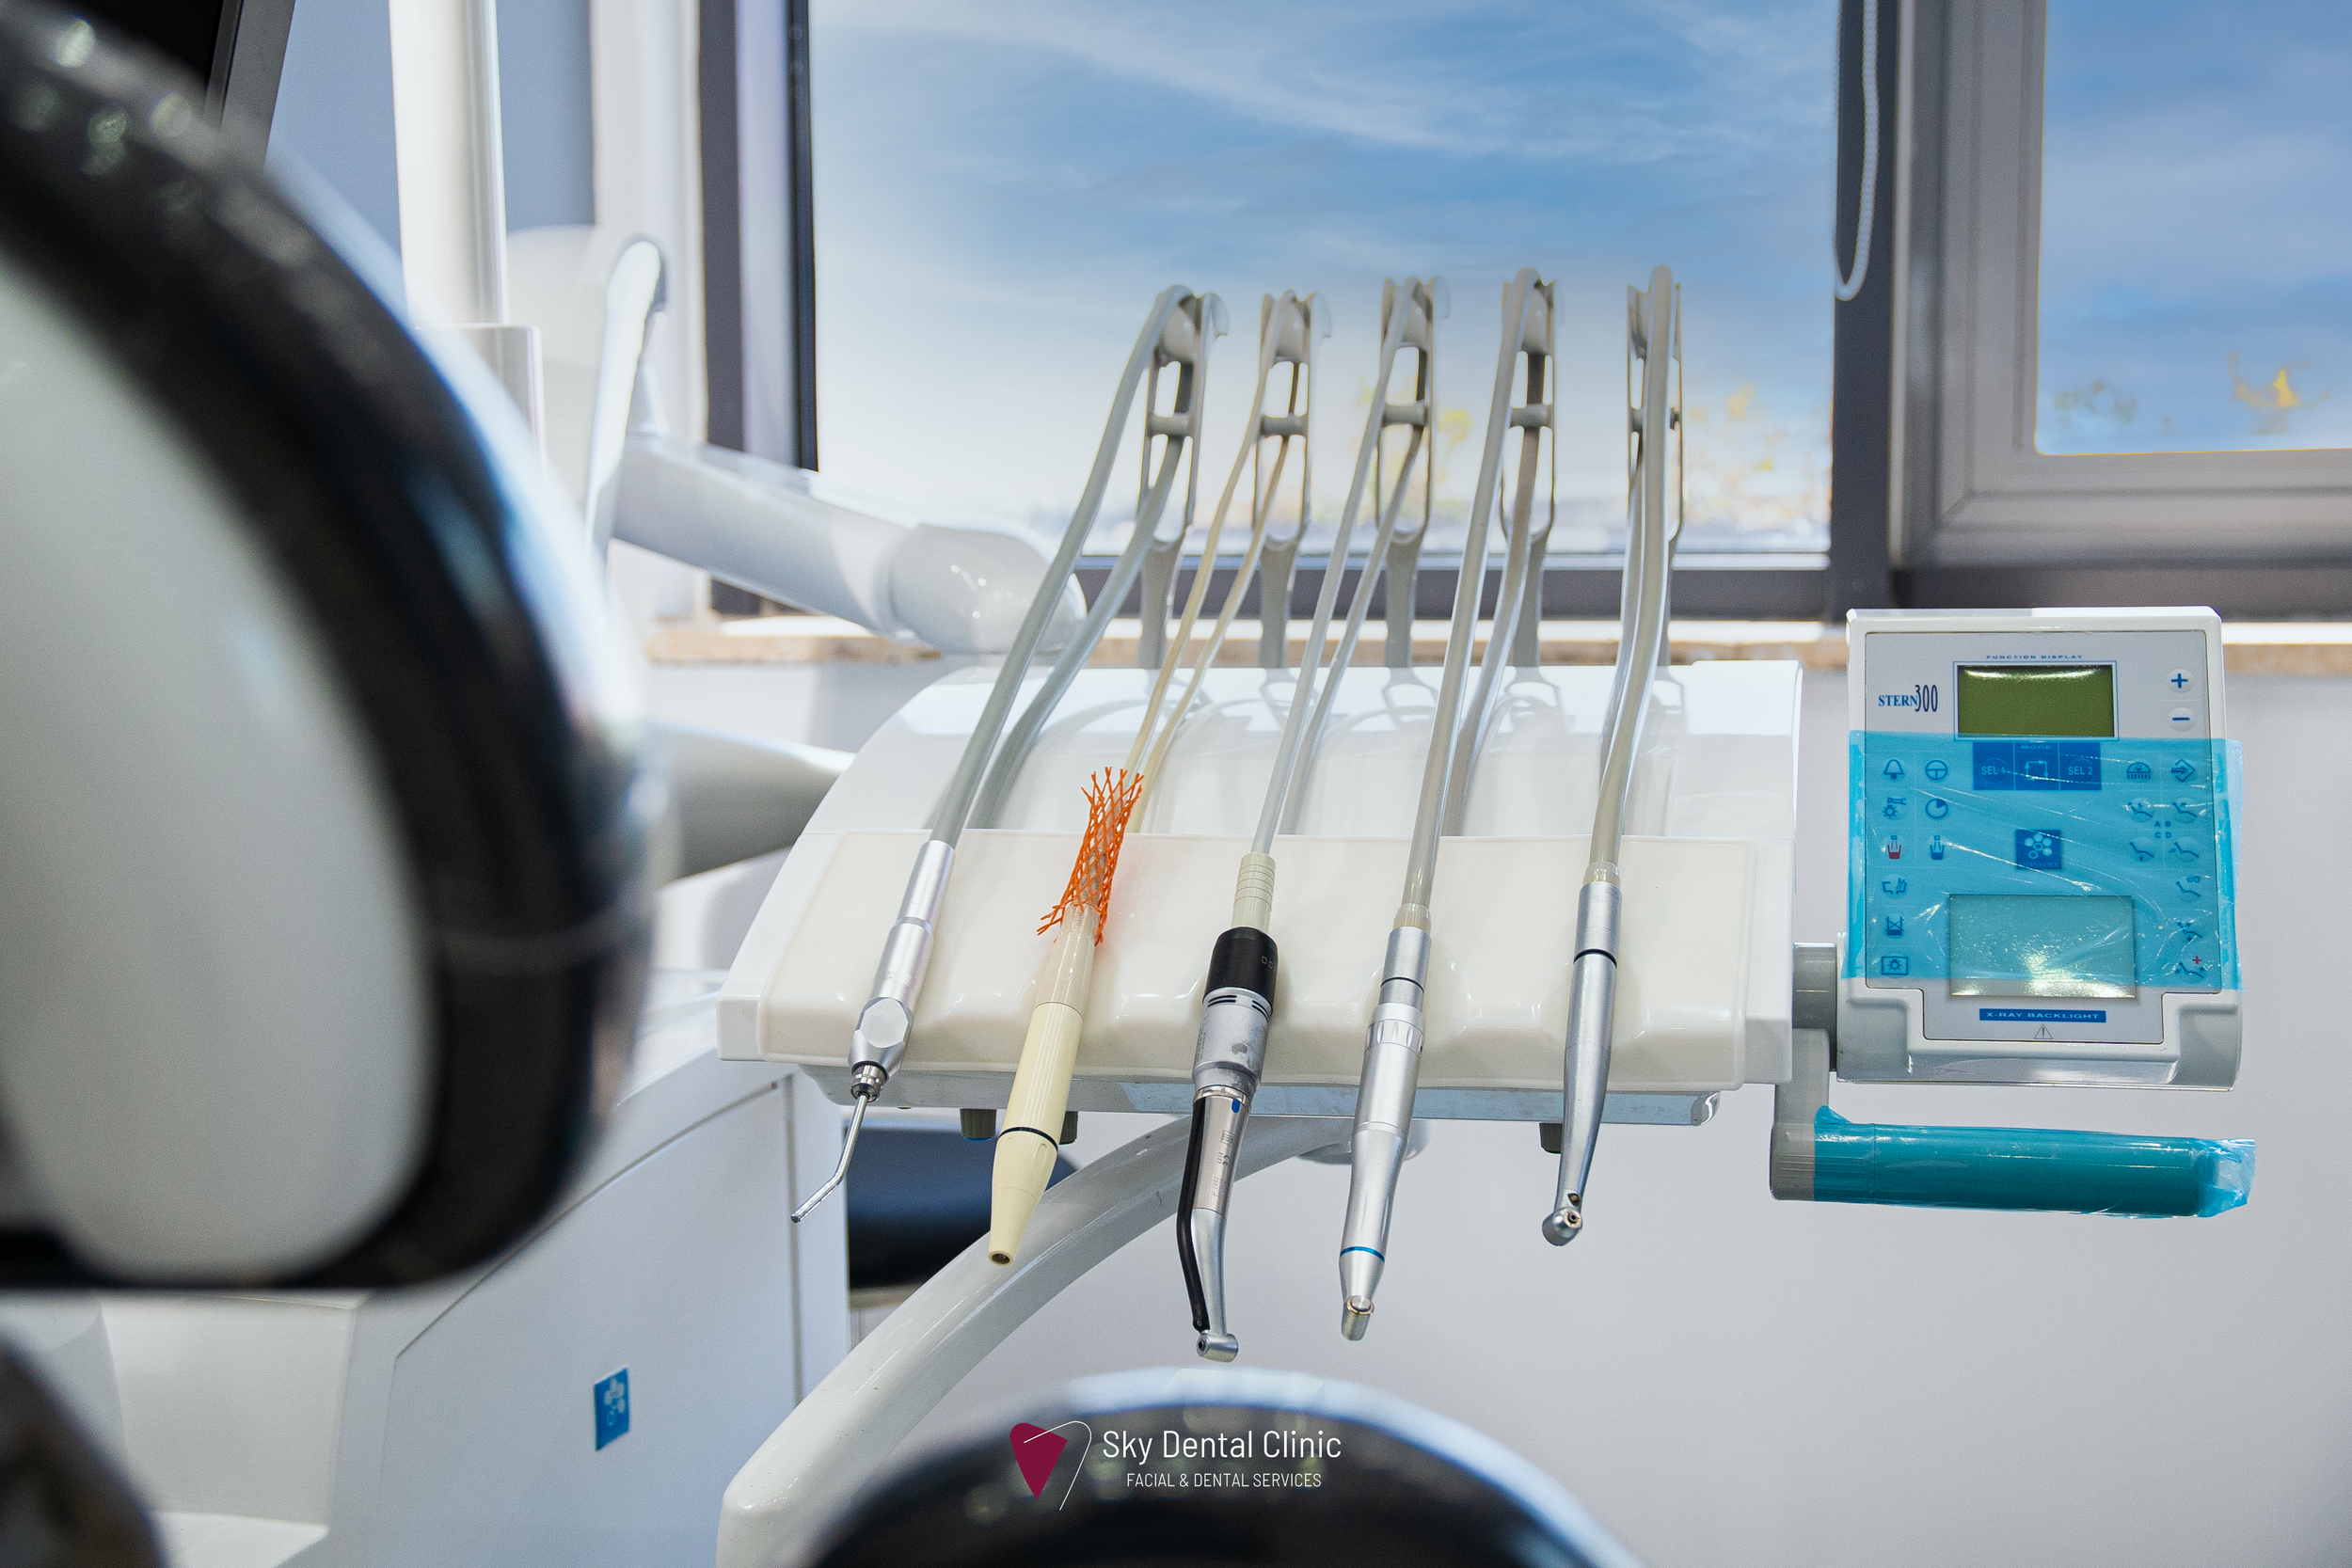

Comprehensive Dental Care in Amman, Jordan

At Sky Dental Clinic, we are committed to providing personalized, state-of-the-art dental care. Led by Dr. Faisal Mohammad Ali Qaoud, a specialist in dentistry and facial aesthetics, our clinic offers a wide range of services including cosmetic dentistry, periodontal surgery, teeth whitening, and Hollywood smile treatments. With a focus on the latest advancements in dental technology, we strive to deliver tailored solutions that meet the unique needs of each patient.

At our dental practice, we are committed to delivering exceptional care with a focus on precision, technology, and patient comfort. Our team of experts strives to exceed your expectations by providing personalized treatments tailored to your oral health needs.